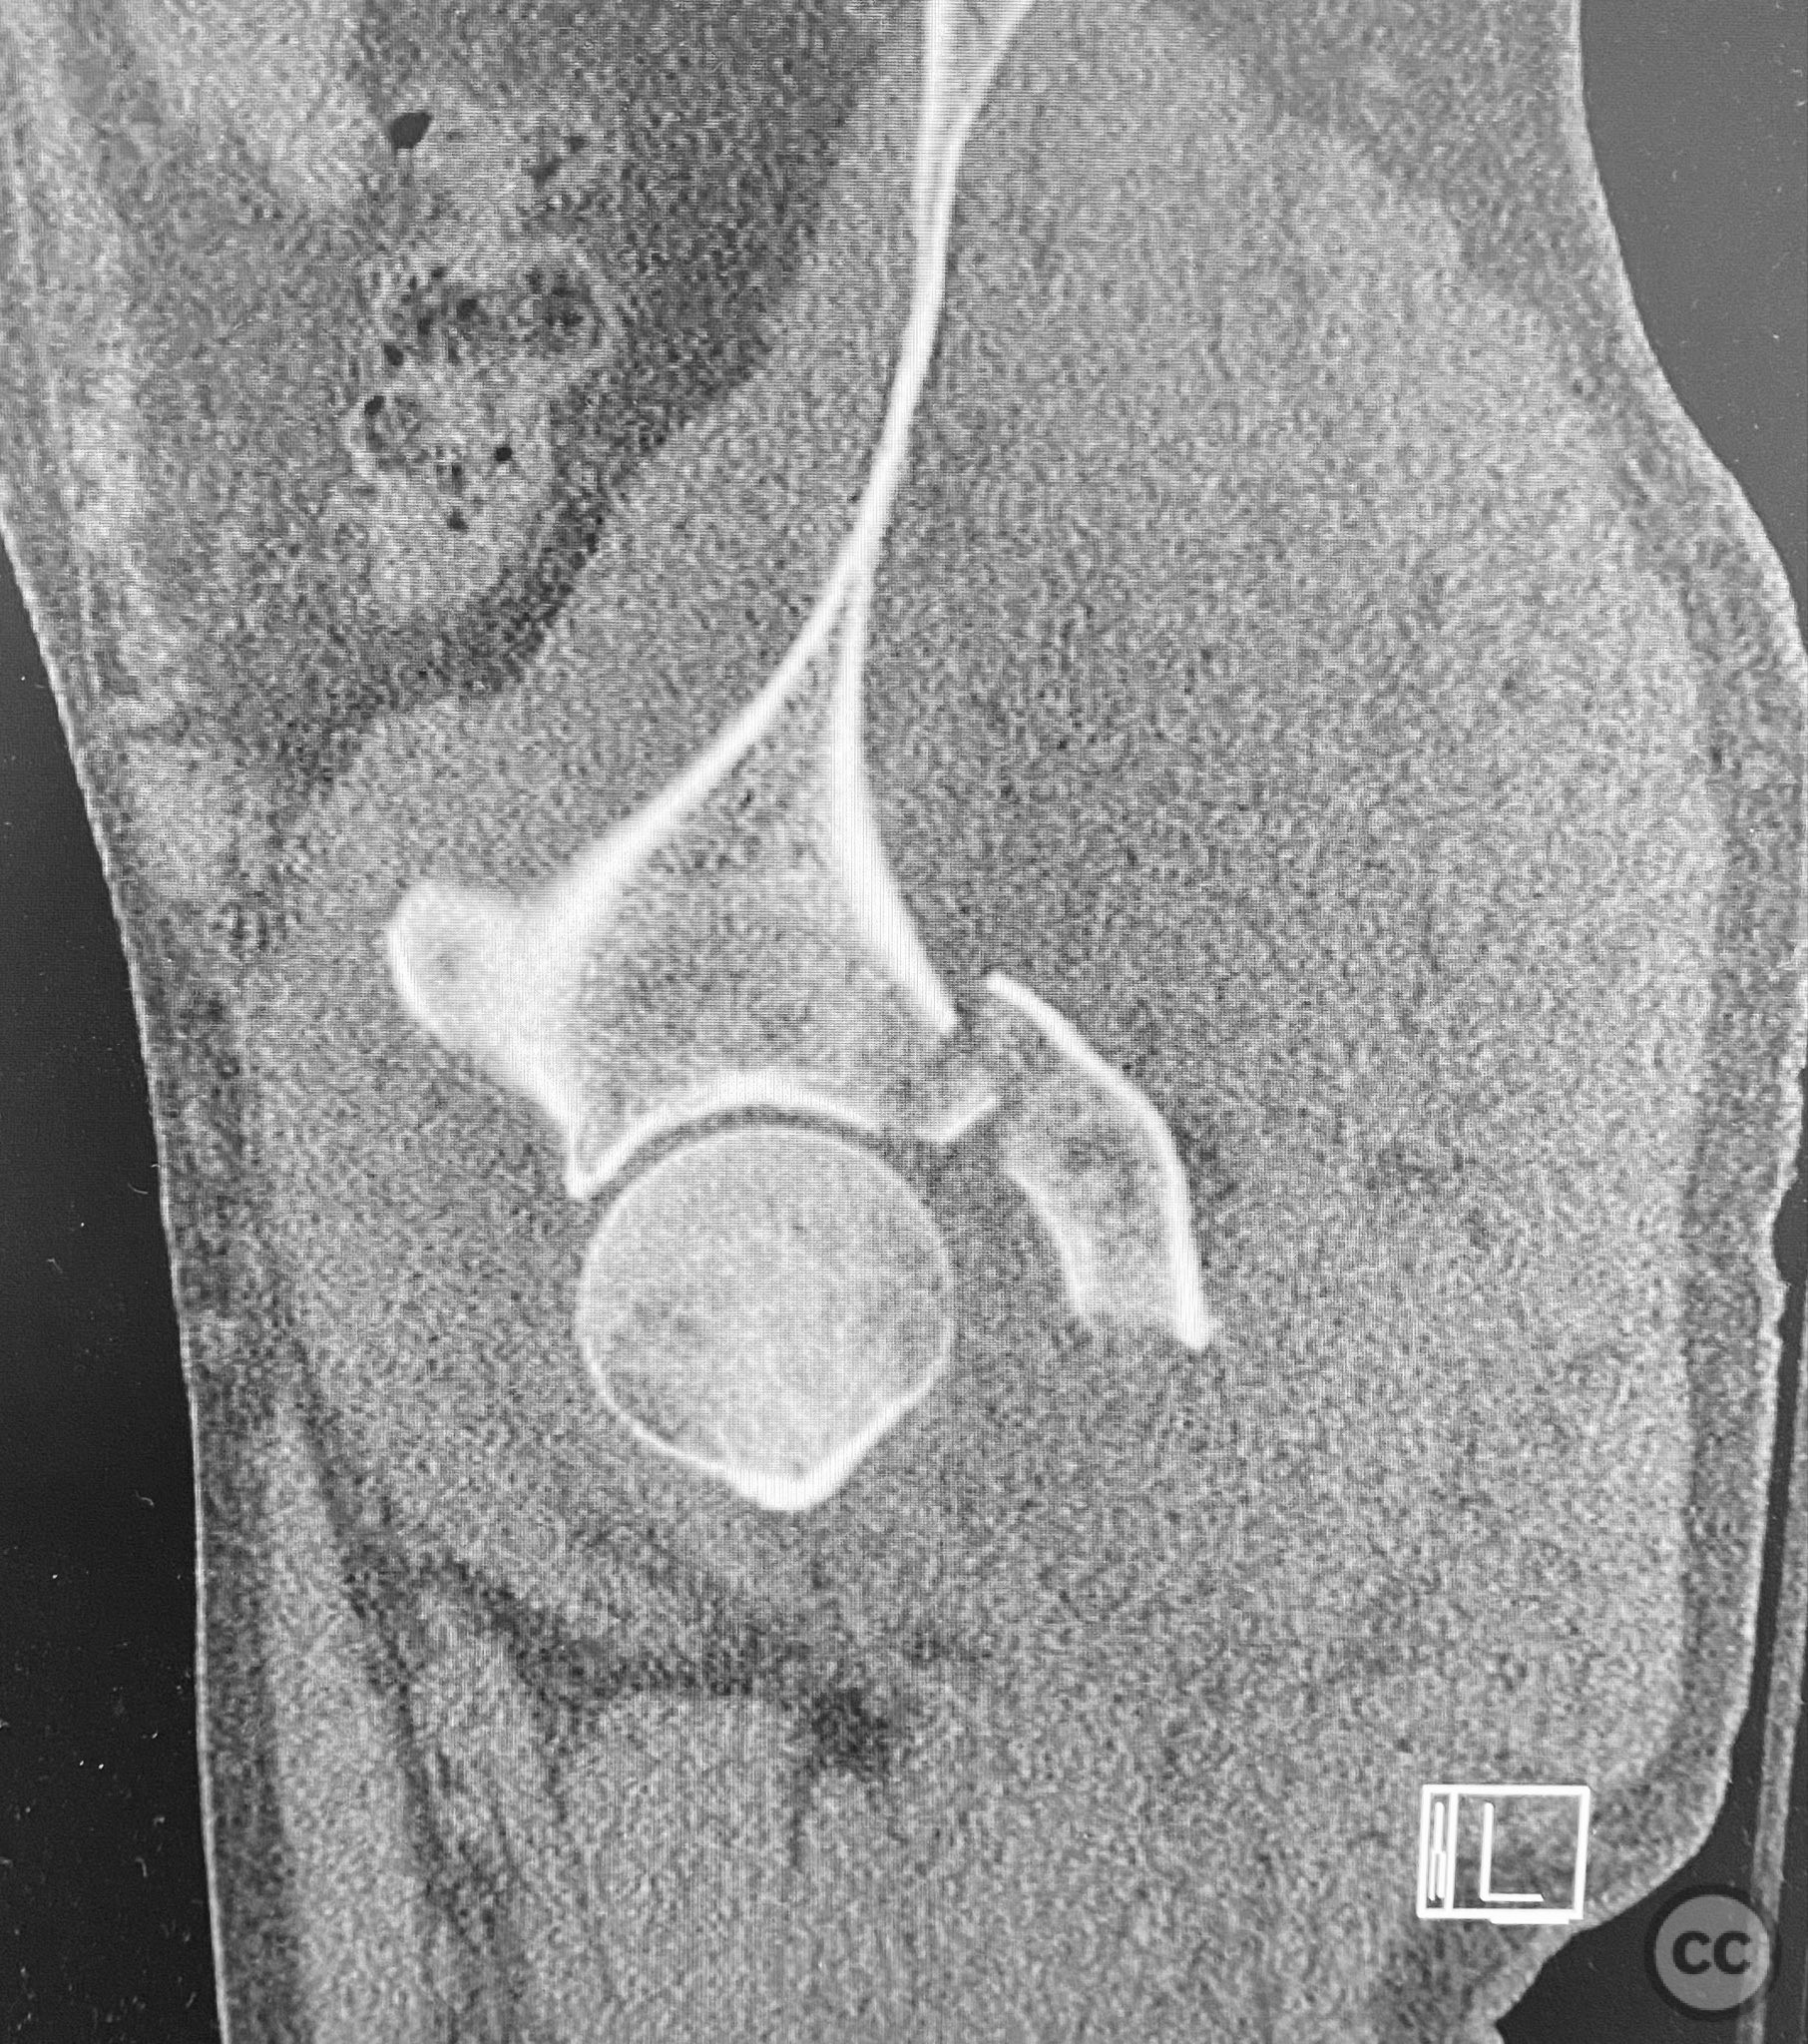

Clinical and radiological findings:  A patient presented with a seemingly non-comminuted, wide, and long posterior wall (PW) acetabular fracture fragment. Axial computed tomography (CT) images demonstrated the thickness of the PW fragment, the articular surface, and multiple areas of subchondral impaction. Preoperative planning identified the size, location, and depth of the impaction zones, as well as an essentially nondisplaced transverse acetabular fracture line, which was not readily apparent on initial imaging. No significant displacement of the transverse component was noted. The AO/OTA classification is 62-B1.3 (posterior wall and transverse acetabular fracture).

Planning remarks:  The preoperative technical plan included a prone Kocher-Langenbeck (KL) approach to access the posterior column and wall. The plan entailed elevation and reduction of impacted articular fragments, bone grafting of subchondral defects, anatomical reduction and provisional fixation of the posterior wall fragment, and definitive fixation with a contoured plate. Intraoperative fluoroscopy was planned to guide additional screw placement through the plate to stabilize both the posterior wall and the transverse fracture line. A supplementary medial plate was planned to augment fixation of both the posterior wall and transverse components.

Intraoperatively, elevation and reduction of impacted articular fragments were performed, followed by bone grafting of subchondral defects. The posterior wall fragment was anatomically reduced and initially stabilized with a contoured plate. Intraoperative fluoroscopy (obturator oblique view) was utilized to guide placement of an additional screw through the plate above the joint, traversing both the posterior wall fragment and stabilizing the transverse fracture line. A supplementary medial plate was applied to further support both fracture components. Postoperative CT imaging confirmed satisfactory reduction of both the posterior wall and transverse fractures, as well as restoration of articular congruity in previously impacted areas. Consideration is given to whether initial reduction and lag screw fixation of the transverse component prior to plate application may have improved reduction; however, final imaging demonstrated acceptable alignment.